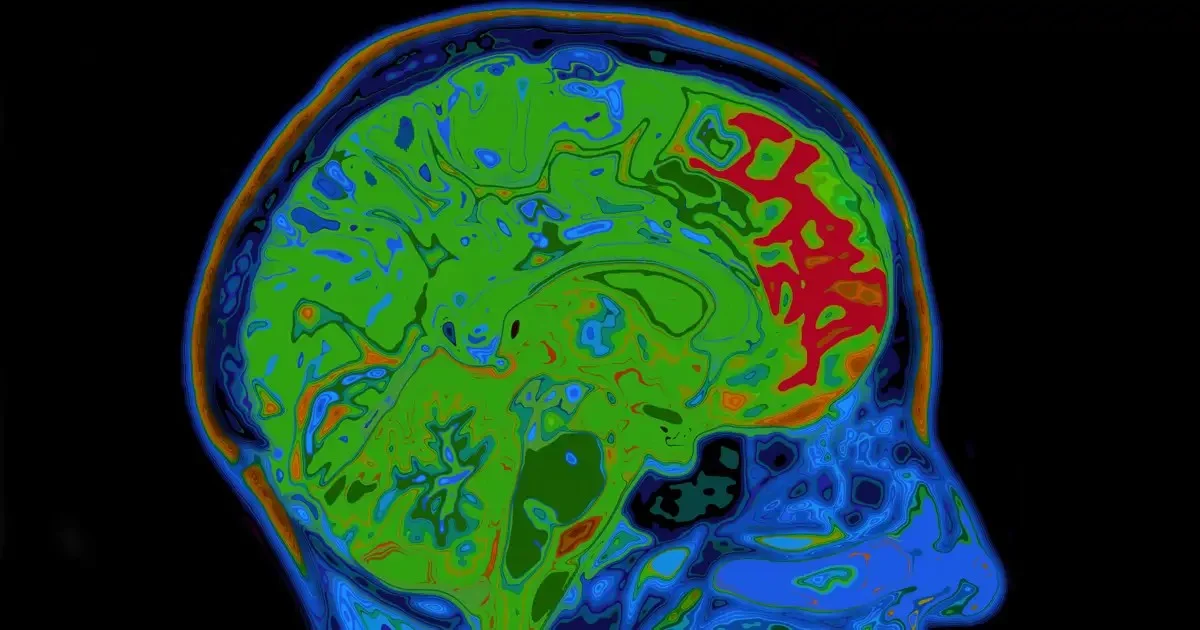

Haben Sie sich jemals gefragt, warum ein langer Arbeitstag oft den Drang nach einem Drink oder einer Zigarette nach sich zieht? Diese Verhaltensweisen, obwohl ungesund, sind tief in unserem Gehirn verankert und aktivieren das Belohnungssystem. Dies ist kein Zufall – ein Team von Forschern der Georgetown University hat ein äußerst bedeutendes neurobiologisches Mechanismus aufgedeckt, das die Bildung guter und schlechter Gewohnheiten beeinflusst.

In ihrer Studie identifizierten die Wissenschaftler ein Protein namens KCC2, das eine entscheidende Rolle bei der Geschwindigkeit spielt, mit der unser Gehirn Belohnungsassoziationen bildet. Dies ist der Schlüssel zur Erklärung, warum einige Gewohnheiten so hartnäckig sind.

- KCC2 ist entscheidend für die neuronale Chlorid-Homöostase, was bedeutet, dass es die Aktivität der Dopaminneuronen – der „Glückshormone“ – beeinflusst.

- Eine verminderte KCC2-Aktivität führt zu steigenden dopaminergen Reaktionen, was neue Verbindungen zwischen Umwelteinflüssen und positiven Ergebnissen verstärkt.

Dieser Mechanismus des assoziativen Lernens kann jedoch von komplexen Störungen wie Sucht und Depression beeinträchtigt werden. Laut Alexey Ostroumov, der Hauptautor der Studie, können Substanzmissbrauch und andere Faktoren die KCC2-Proteinwerte beeinflussen, wodurch das Gehirn Belohnungssignale missbrauchen kann.

Die Forscher beobachteten beim Versuch mit Mäusen, dass ein mangelndes KCC2 die Lernsensibilität erhöht. Je weniger KCC2 vorhanden ist, desto höher ist die Reaktion der Neuronen, was wiederum zu einer verstärkten Freisetzung von Dopamin führt. Diese koordinierten Dopaminausbrüche gelten als extrem starke Lerngsignale.